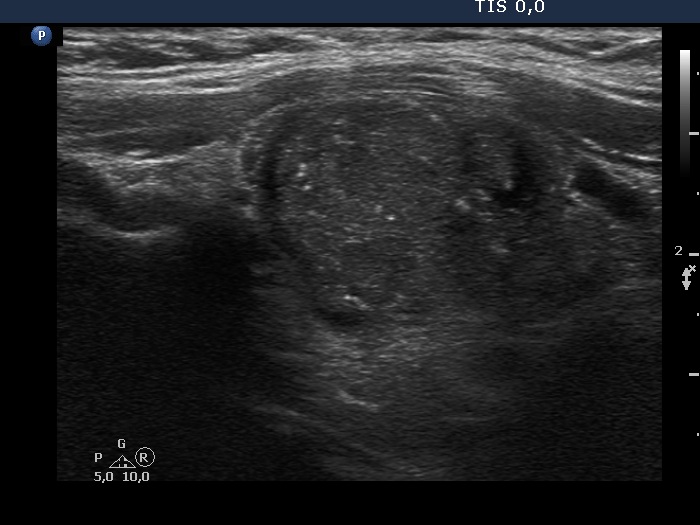

First examination (first row of images):

Clinical presentation: A 37-year-old man was referred for an evaluation of a 'lump in the throat' feeling.

Functional state: subclinical hypothyroidism with TSH 5.01 mIU/L, FT4 13.6 pM/L.

Palpation: the left lobe was suspicious containing a small nodule.

Ultrasonography. The thyroid was moderately hypoechogenic and displayed fibrosis. There was a relatively larger hypoechogenic lesion in the central part, and other smaller ones in the dorsal part of the left lobe. The dimensions of the largest lesion were 11x10x13 mm (width, depth, and length, respectively), the volume was 0.75 mL. The vascularization was not specific.

Aspiration cytology resulted in Hashimoto's thyroiditis. Atypia of unknown significance; the possibility of a Hürthle-cell tumor cannot be excluded.

We told the patient that the risk of malignancy is around 5%. We offered a follow-up examination instead of a surgery and suggested a repeat FNA in six months.